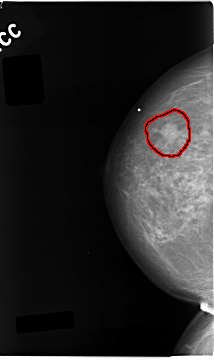

C_0043_1.RIGHT_MLO

RIGHT_CC LINES 4672 PIXELS_PER_LINE 2776 BITS_PER_PIXEL 12 RESOLUTION 50 OVERLAY

FILE: C_0043_1.RIGHT_CC.OVERLAY

TOTAL_ABNORMALITIES 1

ABNORMALITY 1

LESION_TYPE MASS SHAPE IRREGULAR MARGINS MICROLOBULATED

ASSESSMENT 5

SUBTLETY 5

PATHOLOGY MALIGNANT

TOTAL_OUTLINES 1

BOUNDARY